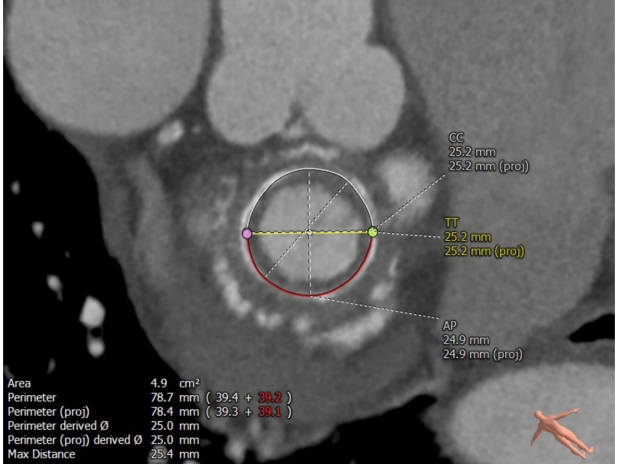

毁损生物瓣瓣架结构 瓣环内径测量

术前经详尽评估患者病情,通过CT重建测量瓣环直径、左室流出道面积。结合之前外科换瓣手术入路,决定采用经心尖途径行二尖瓣“瓣中瓣”手术。术中选用27# Renato®球扩式瓣中瓣,顺利通过心尖途径植入。手术过程顺利,几乎无出血。最终瓣中瓣植入位置理想,功能表现出色,左室造影及经食道超声观察无明显瓣中及瓣周反流。二尖瓣峰值流速由术前2.5m/s降至1.6m/s,平均跨瓣压差由11mmHg降至5mmHg。

患者男性,69岁,2008年因“马凡综合征”行MVR(生物瓣)+David手术,植入29# Hancock II生物瓣一枚。2022年1月患者出现活动后胸闷、气促并逐渐加重。心脏超声示二尖瓣生物瓣置换术及升主动脉人工血管术后,二尖瓣中重度反流,考虑二尖瓣生物瓣毁损。患者STS评分8.007%,属于常规外科再次换瓣手术高风险患者。